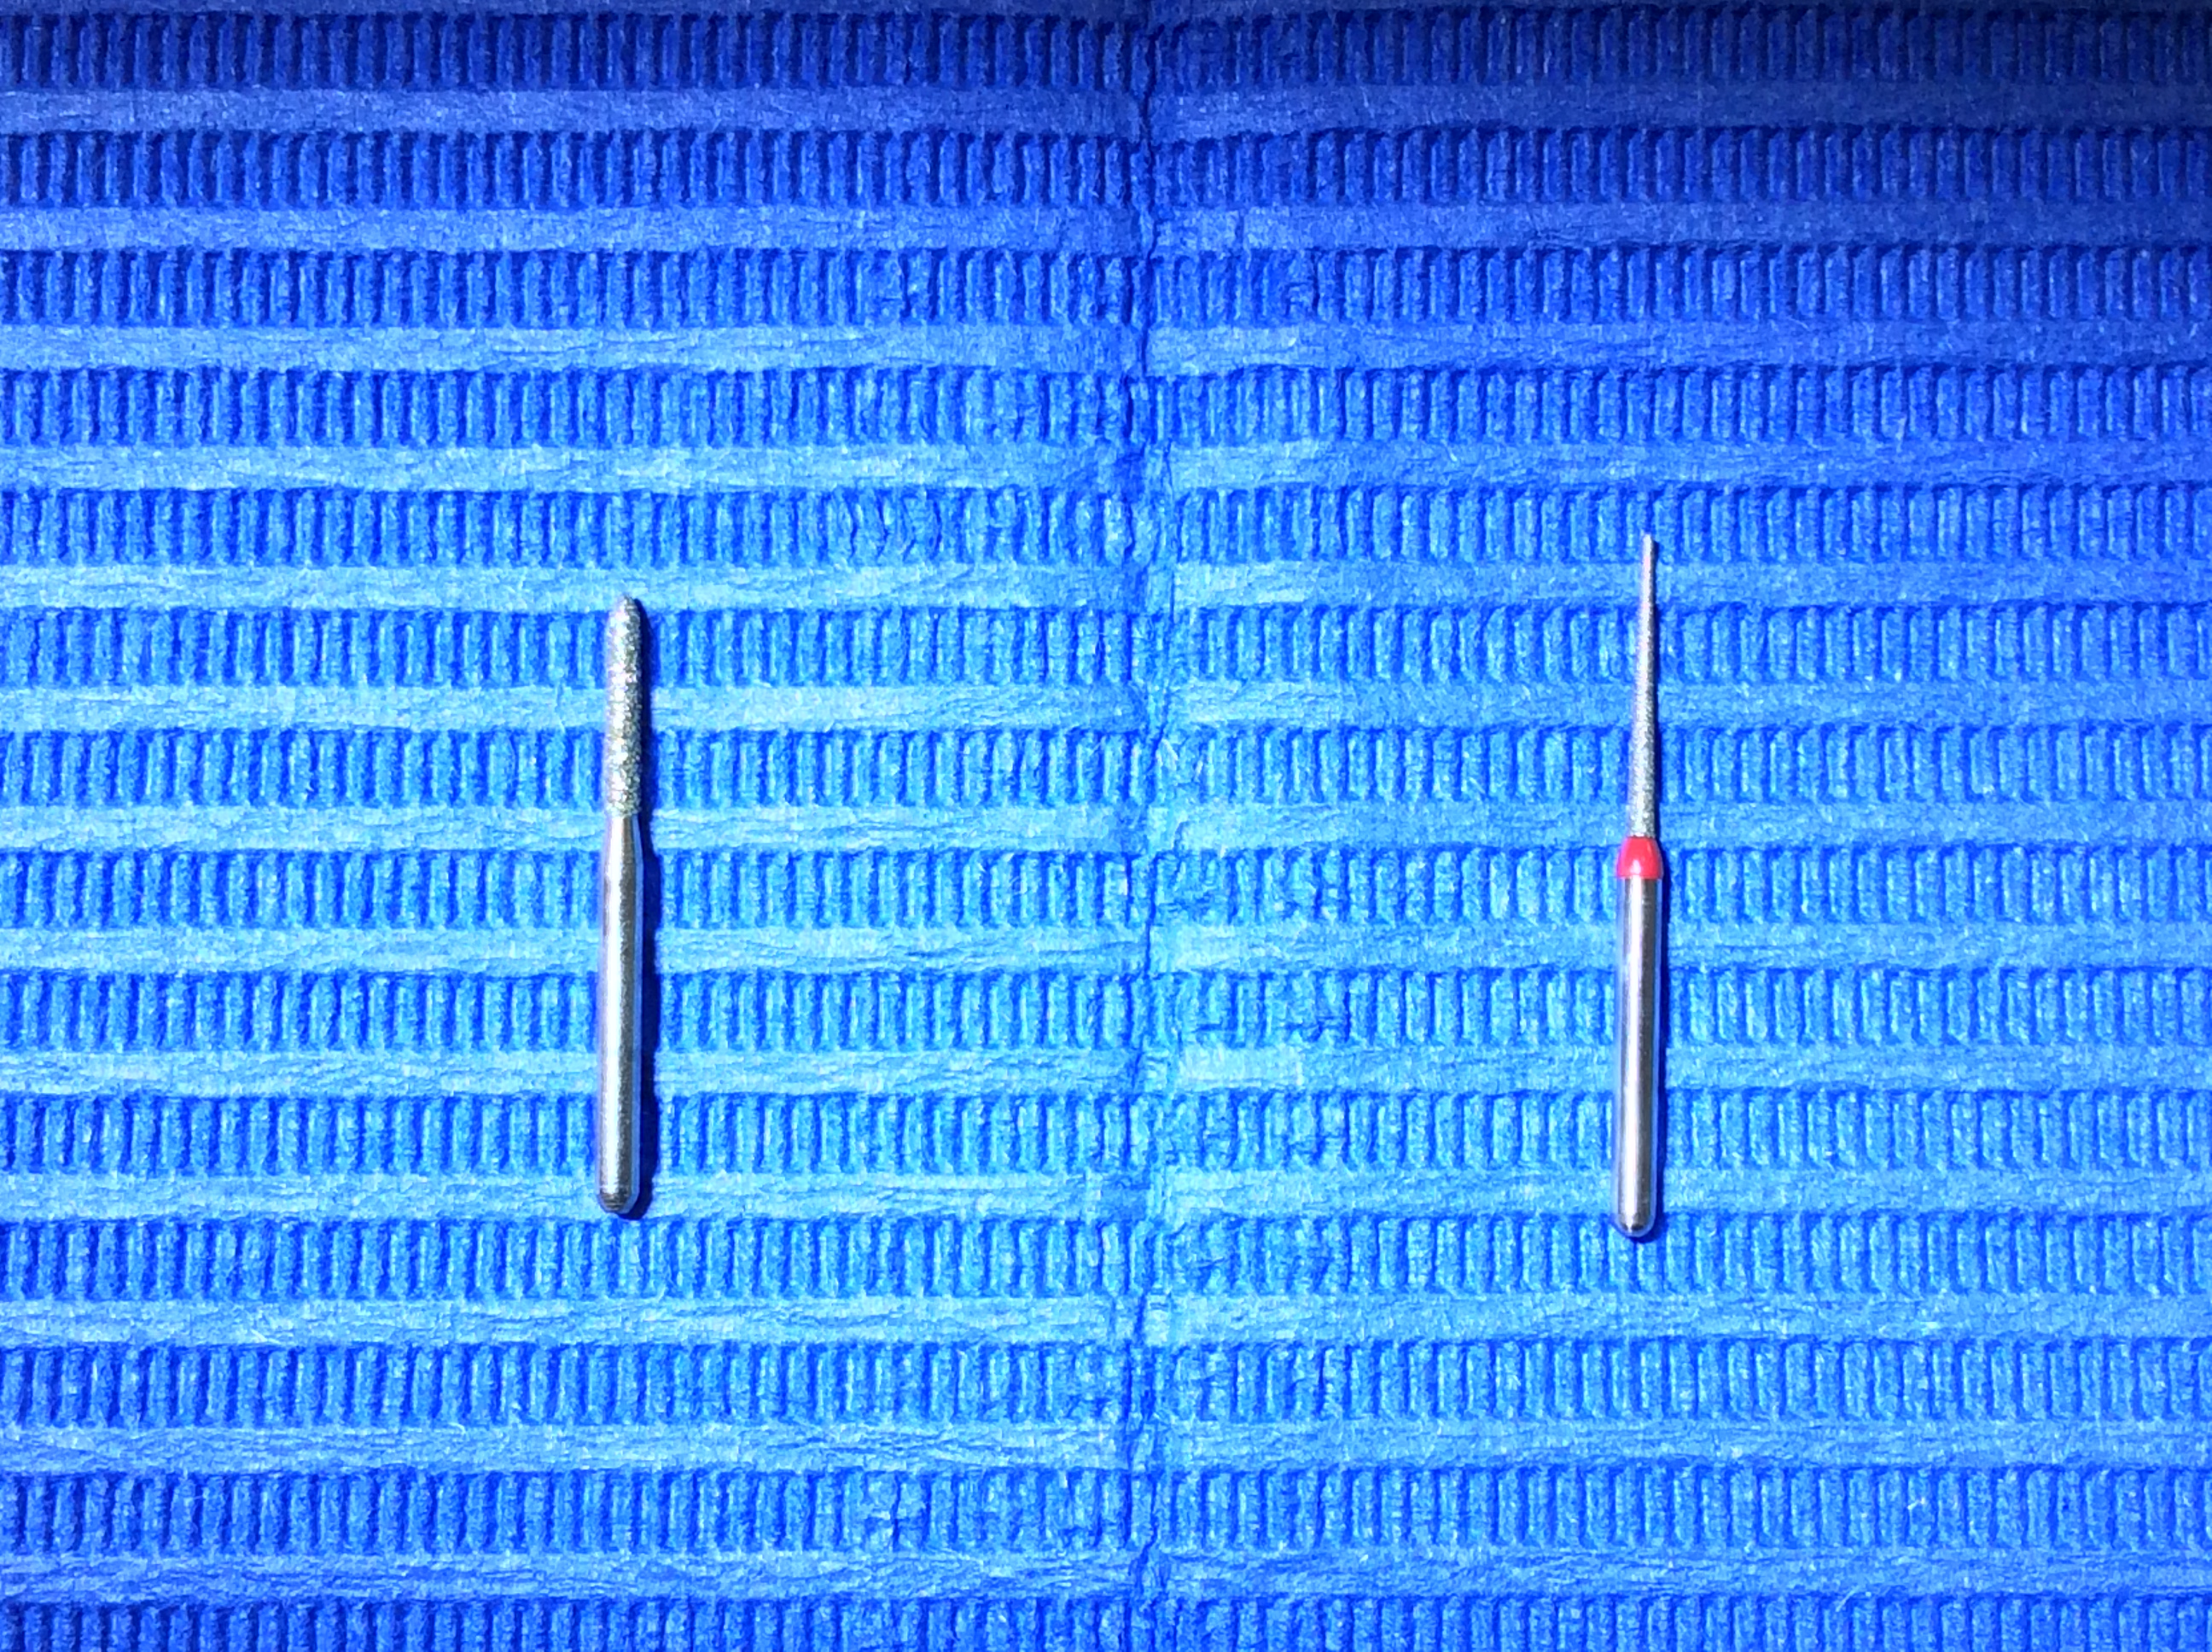

IPRの量が多い時は虫歯を削るような太いバーでは削らず、削りすぎや虫歯、しみるのを防ぐために専用の細いバーで削ります。

左が虫歯を削るバーで、右が専用の細いバーです。↓